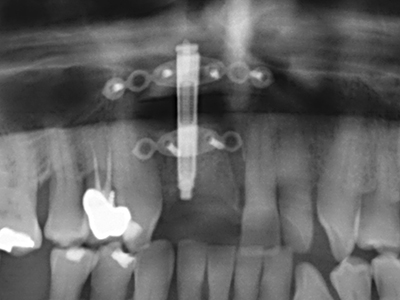

Indication: Preparation near nerves

As noted above, indications for piezosurgery can also be found in the field of conservative dental surgery. Special working tips simplify the exposure of root tips and make it easier to protect nerves and sinus mucous membranes, particularly in the lower premolar and upper posterior tooth regions. Angled diamond tips are used to precisely prepare the resection cavity for the retrograde root filler material for unsealed apical obturation. The ultrasonic technology means the tips can be very slender, which improves the view and the size of the access cavity. As a result, the application of ultrasonic surgery for this indication is one of the standard procedures for apical resection (Del Fabbro, Tsesis et al. 2010, Scarano, Artese et al. 2012).

Indication: Apical resection

When surgical procedures are performed on bone in the immediate vicinity of sensitive structures such as blood vessels or nerves, rotary instruments pose a significant risk of iatrogenic injury. Piezoelectric devices can be helpful for preparation of bone covers and removal of hard tissue close to nerves, particularly for exposure of nerves after iatrogenic injury but also during nerve lateralization for resective and reconstructive procedures or implant placement (Fig. 17-20). Light contact between the piezotip and the nerve does not generally result in damage but proceeding incautiously with saw-like motions or attachments where a residual bone substrate remains may cause temporary or even permanent nerve damage. However, the risk of damage is considered to be substantially lower than when using saws or milling instruments (Pereira, Gealh et al. 2014).